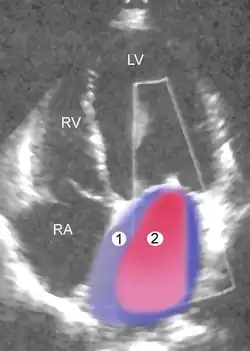

Schwere MI Legende

1 Linker Vorhof (LA) – 2 MI-Jet

LV Linke Herzkammer – RV Rechte Herzkammer – RA Rechter Vorhof

Die Farbdoppler-Echokardiografie (s. Abb.) zeigt eine vorhandene Mitralinsuffizienz als (meist blau dargestellte) Farbwolke im linken Vorhof, die als Insuffizienzjet oder Regurgitationsjet bezeichnet wird. Breite und Ausdehnung dieser Farbwolke erlauben bereits eine grobe Abschätzung des Schweregrades der Insuffizienz. Darüber hinaus können meist bei der Echokardiografie bereits der zugrundeliegende Mechanismus (Ringdilatation, inkompletter Klappenschluss, Endokarditis, Prolaps, flail leaflet, „unklar“) und die Lokalisation eventueller Klappenveränderungen dokumentiert werden.[20]

Farbdopplerdarstellung einer Mitralklappeninsuffizienz